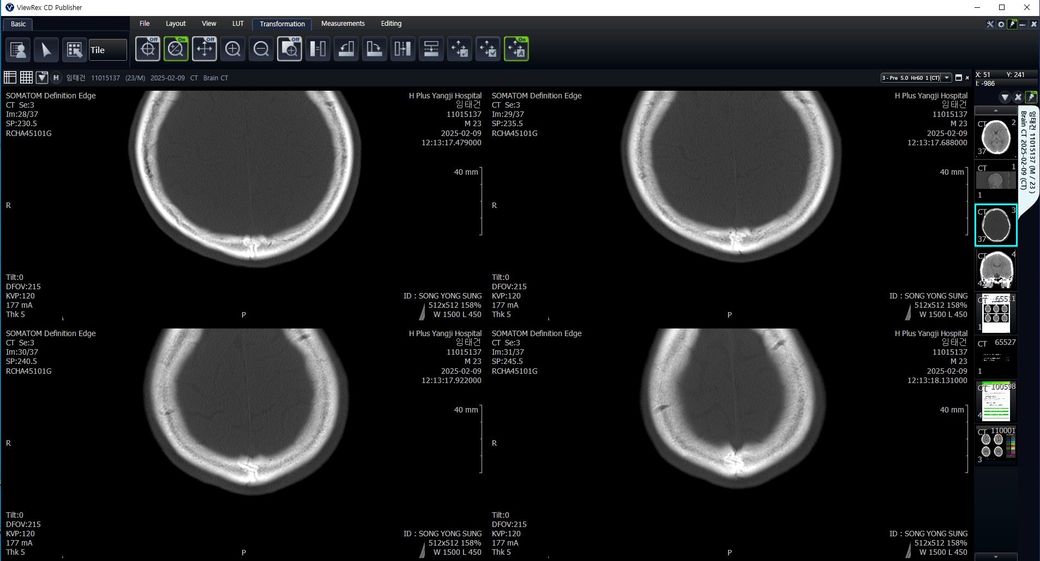

두개골 수술 또는 골절 의심되는 상황인데 엑스레이와 ct사진을 한번 봐주실 수 있나요?

2~3일 정도 기억이 없었는데 그때 머리를 다쳤는지 바로 x-ray와 ct를 찍어봤는데 한번 봐주실 수 있을까요? 진단 목적이 아닌 확인 목적입니다

빨갛게 동그라미 친 곳은 금속물질이 의심도는 부근입니다